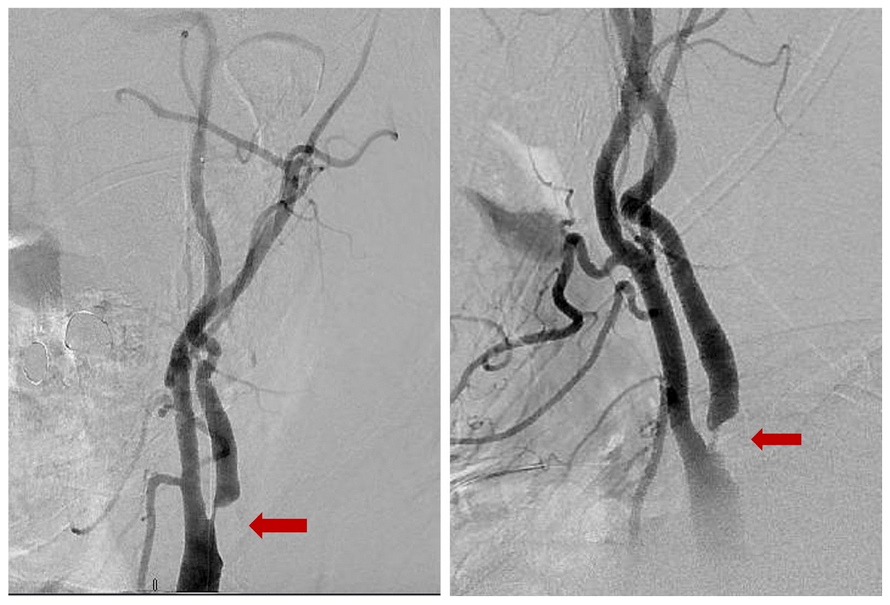

Diagnostic Cerebral Angiogram: This is the most accurate measure, but it is a more invasive diagnostic procedure (includes inserting a catheter) that often only is used if there is no clear answer from a simpler test.

Figure 2. Carotid Angiogram demonstrating severe left internal carotid artery origin stenosis (red arrow)